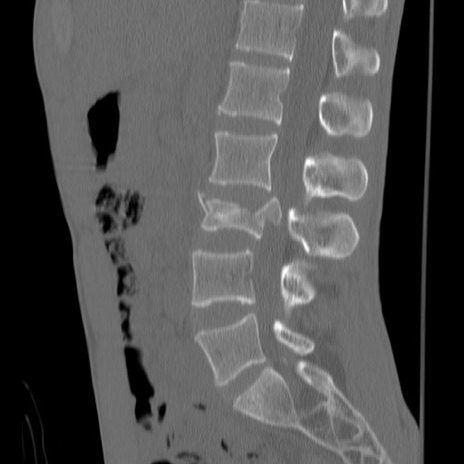

症例3 腰椎CT(矢状断像)

腰椎CT

冠状断像